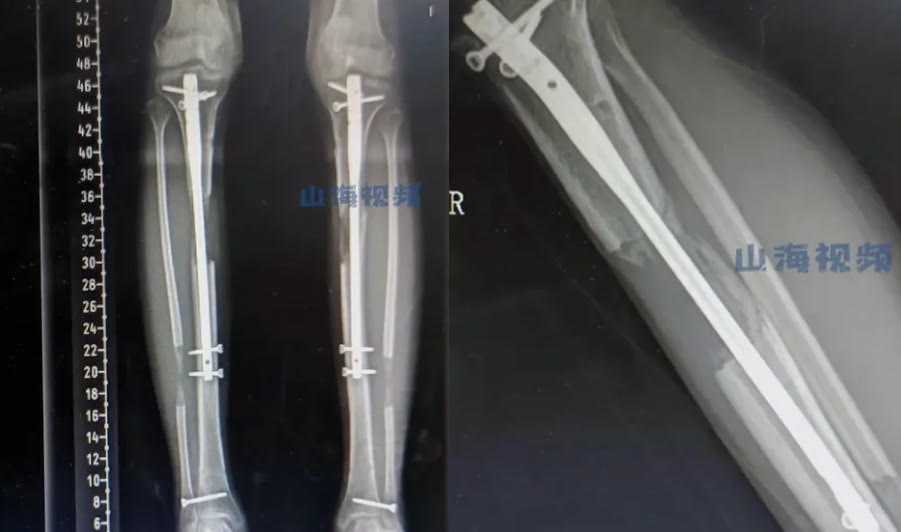

根據《山東商報》山海視頻報導,中國江西南昌一名19歲少女近期做完「斷骨增高」手術後,因反覆感染,目前無法正常行走,原本154公分的她不滿意自己身高,跑到湖南某私立醫院進行「脛腓骨延長術」,結果術後左下肢竟反覆感染,甚至造成雙下肢關節僵硬,讓她無法正常行走,這才尋求其他大型教學醫院治療。

然而在照完X光檢查後,醫生指出目前少女腓腸肌被拉得非常纖細,神經也被拉扯,不僅腳呈現下垂無法翹起,還須靠拄拐杖才能行走,認為少女「要恢復還是比較困難的」。